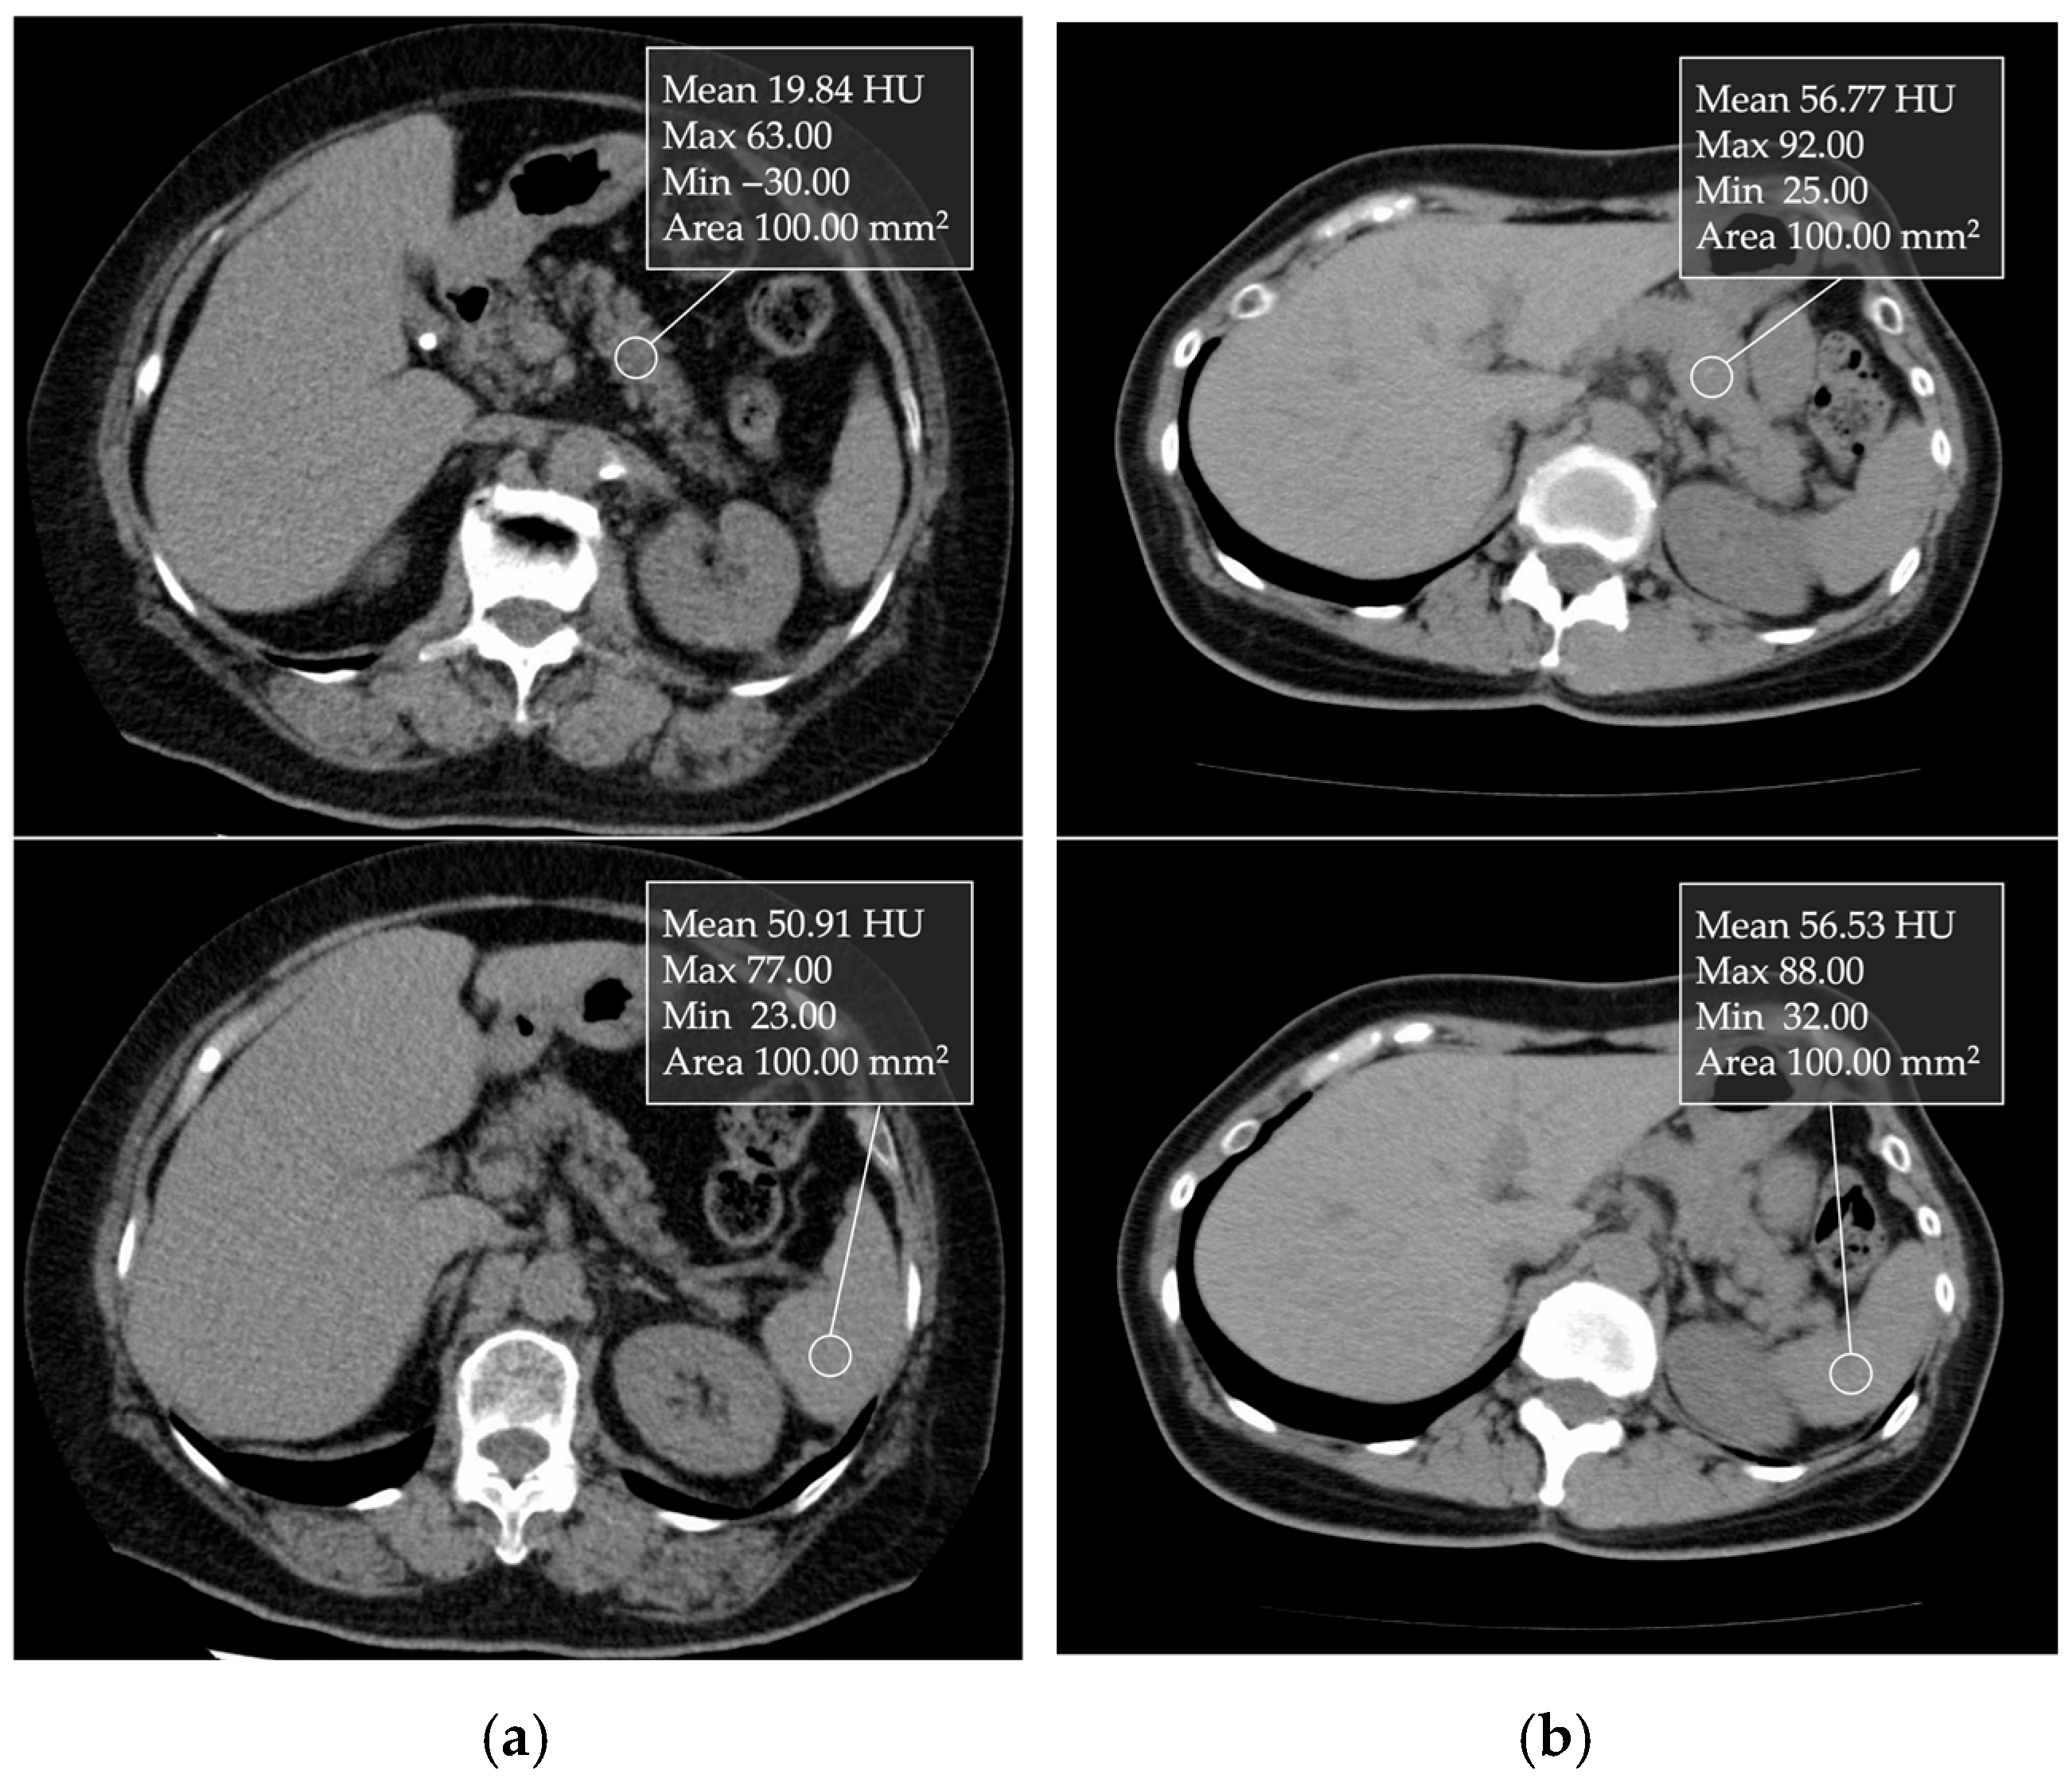

5.3. Computed Tomography (CT)

- Kim, S.Y.; Kim, H.; Cho, J.Y.; Lim, S.; Cha, K.; Lee, K.H.; Kim, Y.H.; Kim, J.H.; Yoon, Y.S.; Han, H.S.; et al. Quantitative assessment of pancreatic fat by using unenhanced CT: Pathologic correlation and clinical implications. Radiology 2014, 271, 104–112. [Google Scholar] [CrossRef] [PubMed]

- Mori, N.; Sakurai, N.; Iizawa, H. Predicting postoperative pancreatic fistula after distal pancreatectomy by measuring the CT value ratio of future pancreas remnant to spleen (P/S ratio) in preoperative unenhanced CT images. Jpn. J. Gastroenterol. Surg. 2019, 52, 485–493. [Google Scholar] [CrossRef]